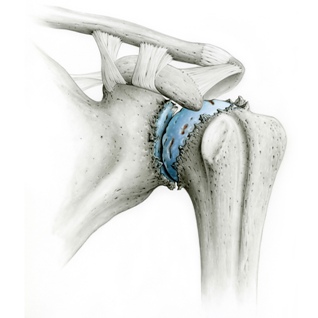

Behandlungen von Schulter-, Ellbogen- und Handgelenks-verletzungen sind oft sehr anspruchsvoll und komplex. Deshalb ist mit einer längeren Erholungsphase in vielen Fällen bis zu 6 Monaten und länger zu rechnen, beispielsweise bei Operationen bei Schulterluxationen und Instabilitäten am Schultergelenk, Schultergelenksarthroskopien bei Einklemmungssyndromen, Rekonstruktion der Rotatorenmanschette, Kunstgelenk-ersatzoperationen an der Schulter. Die Entwicklungen auf diesem Fachgebiet sind enorm vorangeschritten, sodass heute viele Eingriffe in entsprechender arthroskopischer oder minimal-invasiver Technik durchgeführt werden können. Dies führt in der Regel zu bedeutend kürzeren Spitalaufenthalten und schnellerer Erholung.

Die  wichtigsten Verletzungen und Erkrankungen an Schulter, Ellbogen und Hand: